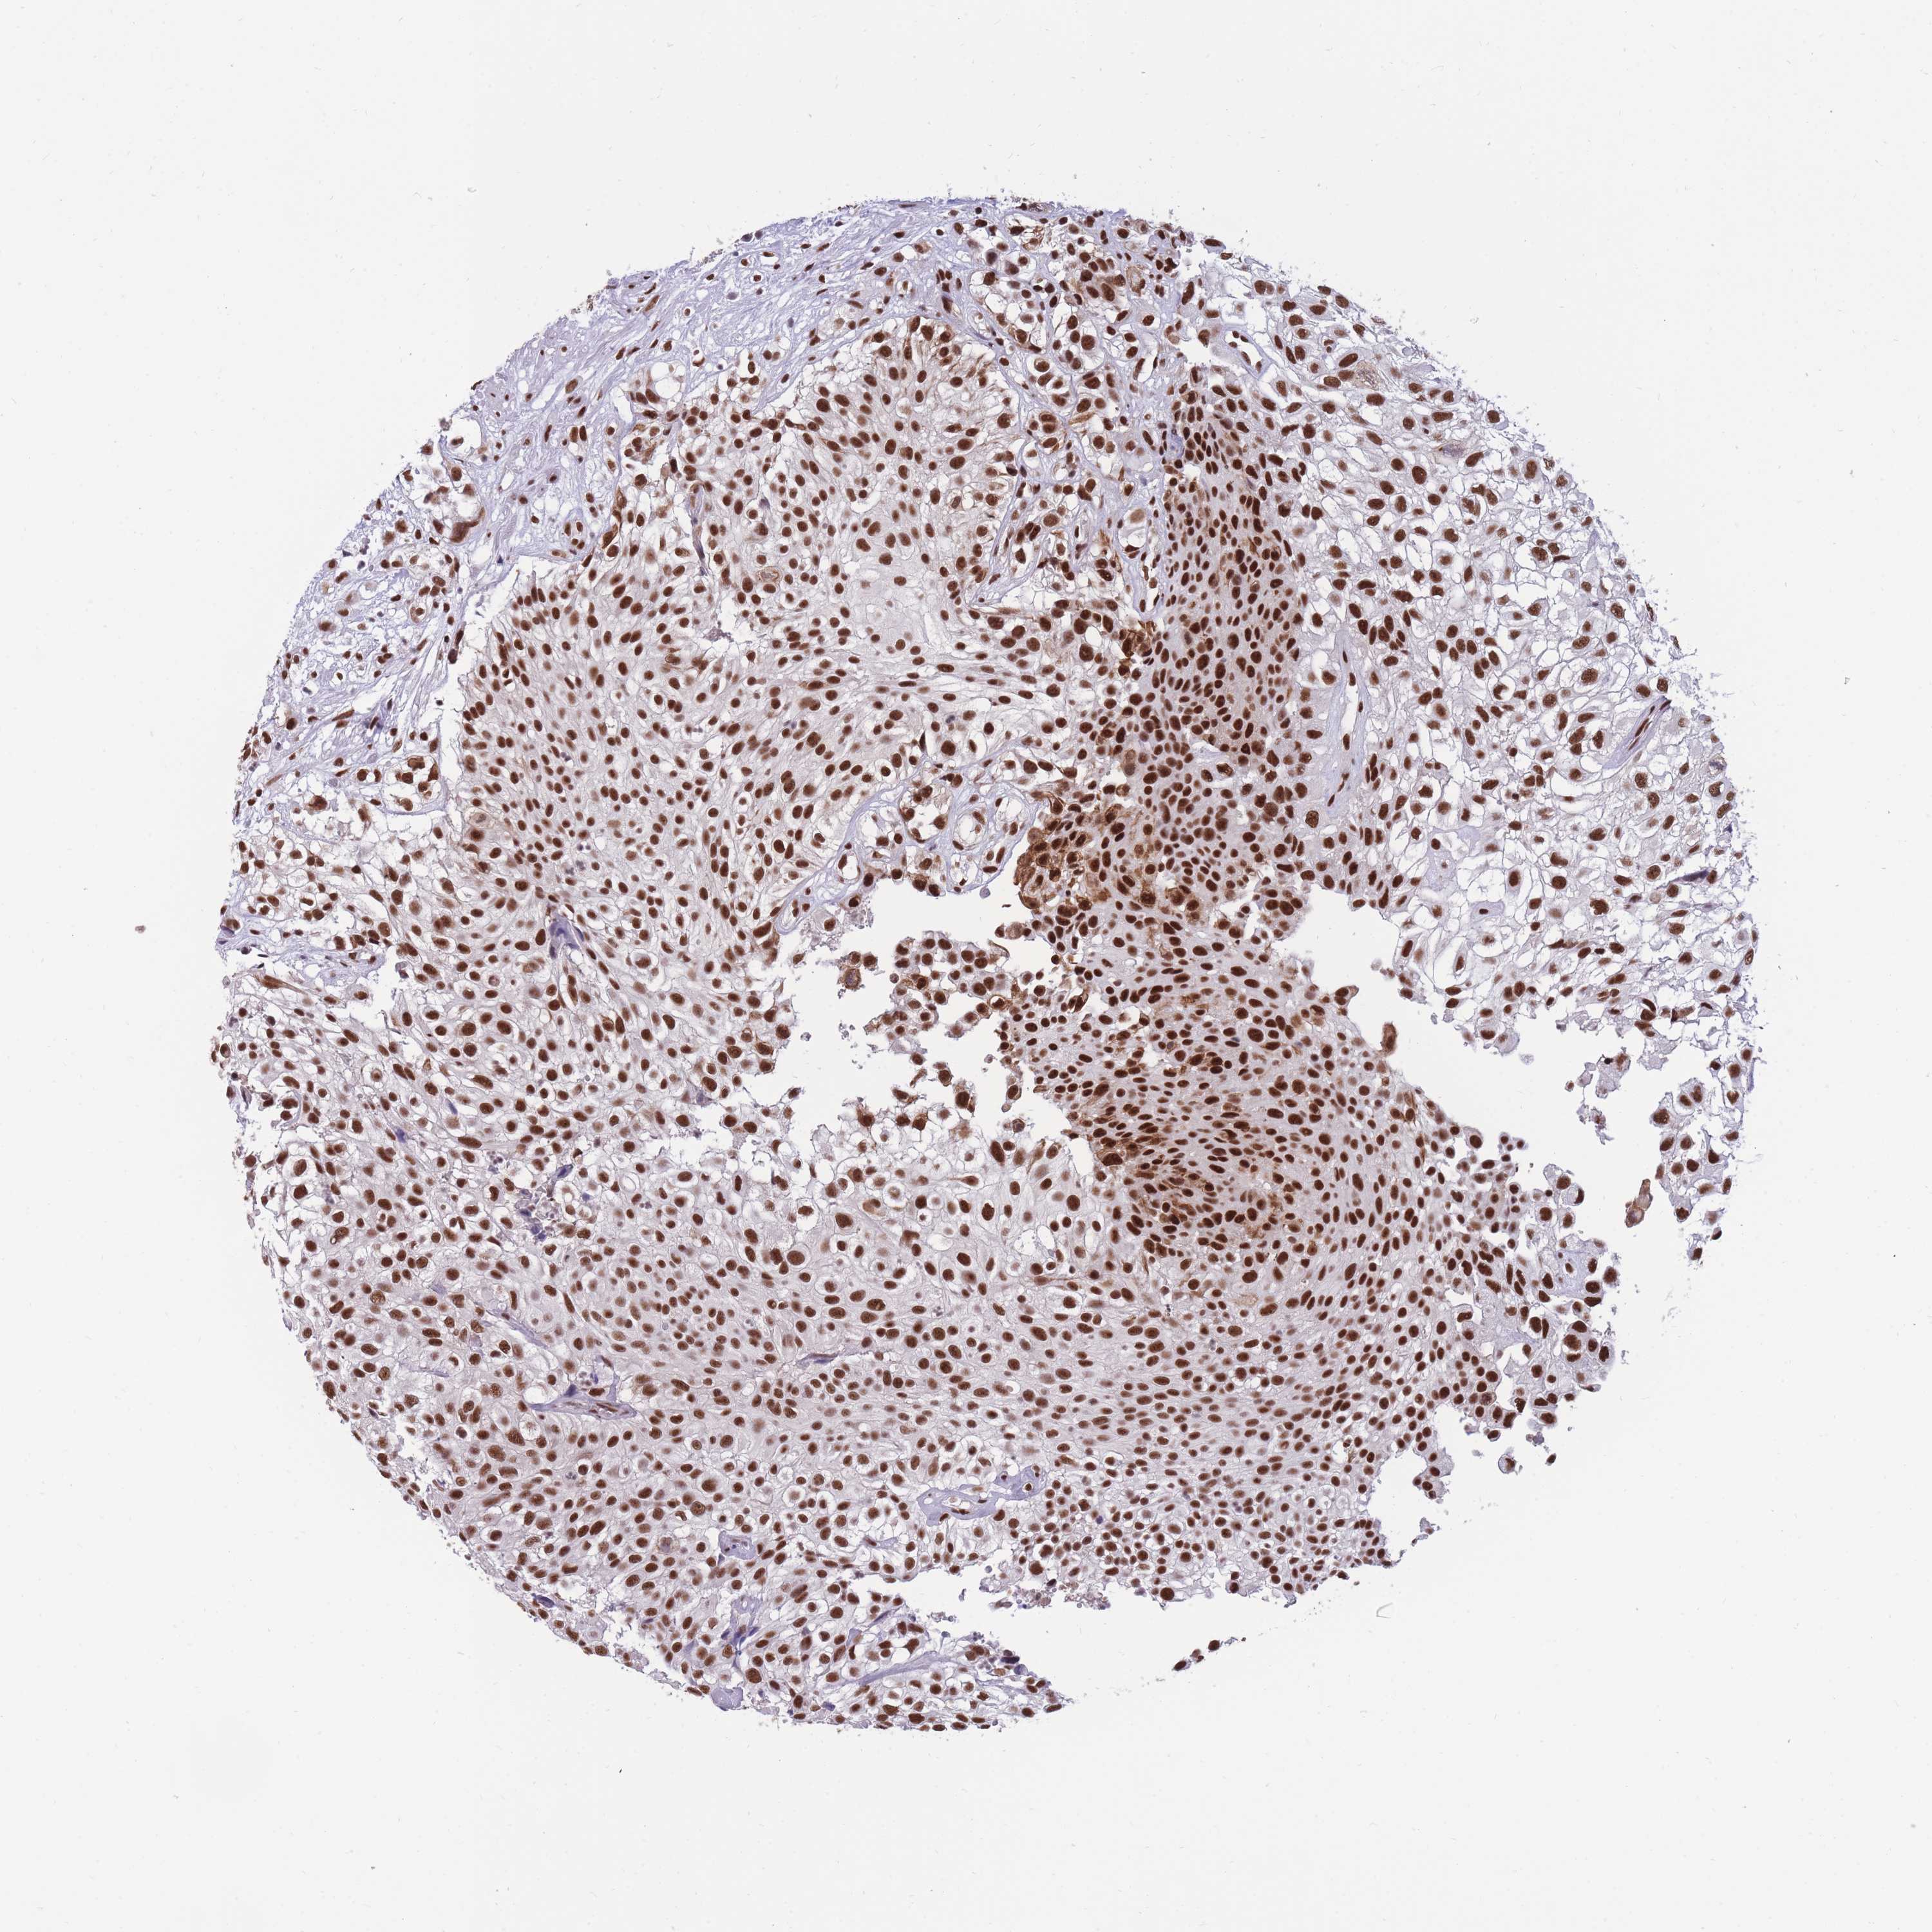

UROTHELIAL CANCER - Protein expressioni

A mouse-over function shows sample information and annotation data. Click on an image to view it in a full screen mode. Samples can be filtered based on level of antibody staining by selecting one or several of the following categories: high, medium, low and not detected. The assay and annotation is described here.

Note that samples used for immunohistochemistry by the Human Protein Atlas do not correspond to samples in the TCGA dataset.

Antibody stainingi

Antibody staining in the annotated cell types in the current human tissue is reported as not detected, low, medium, or high, based on conventional immunohistochemistry profiling in selected tissues. This score is based on the combination of the staining intensity and fraction of stained cells.

Each image is clickable and will lead to virtual microscopy that enables deeper exploration of all samples and also displays staining intensity scores, fraction scores and subcellular localization as well as patient and tissue information for each sample.

Antibody HPA038051

Antibody HPA059070

Antibody CAB012448

Staining

High

Medium

Low

Not detected

Intensity

Strong

Moderate

Weak

Negative

Quantity

>75%

75%-25%

<25%

None

Location

Nuclear

Cytoplasmic/membranous

Cytoplasmic/membranous,nuclear

Urothelial carcinoma, High grade

Urothelial carcinoma, Low grade

Urothelial carcinoma, NOS